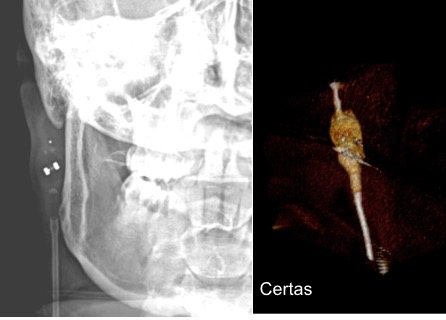

il existe un grand nombre de valves ; il n’est pas toujours aisé de les reconnaitre radiologiquement. voici la liste des plus courantes :

comment reconnaitre radiologiquement le type de valve ?

il est important pour le radiologue qui fait une IRM quel est le type de valve en raison des implications sur l’image et sur le fonctionnement de la valve (en pratique ce surtout les anciennes sophysas ancien modèle qui se dérèglent dans l’IRM).